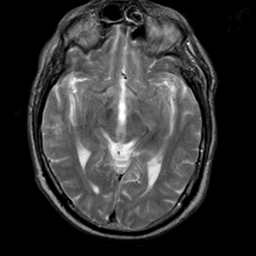

Meningioma, MR Study #2 -- Slice #8

[Home][Help][Clinical] Slice 8